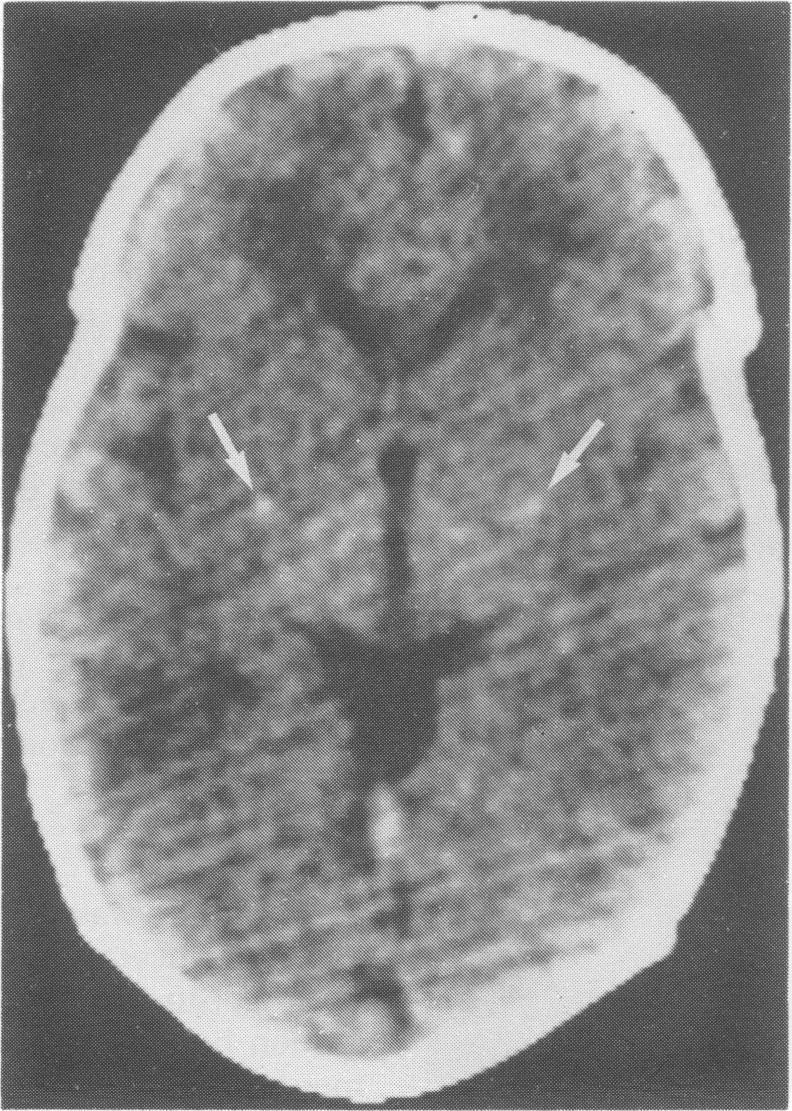

Clinical observations and findings on imaging are reported in six newborns with symmetrical thalamic lesions (STL). In three cases the diagnosis was confirmed by postmortem examination. Characteristic observations in this series and 17 previously reported cases include no evidence of perinatal asphyxia, high incidence of polyhydramnios, absent suck and swallow, absent primitive reflexes, appreciable spasticity at or within days of birth, lack of psychomotor development, and death within days or months. Characteristic pathological findings include loss of neurons, astrogliosis, and 'incrusted' neurons particularly in the thalamus. In two thirds of cases the basal ganglia and brain stem are involved as well. A hypoxic-ischaemic event occurring two to four weeks before birth is most likely responsible for STL. Bilateral thalamic calcification can often, but not always, be demonstrated in the newborn period by computed tomography and/or cranial ultrasound. The presence of these calcifications and the observation of spasticity at birth imply that the responsible insult occurred at least two to four weeks earlier. The small number of published cases with STL suggest that it may be easily missed.